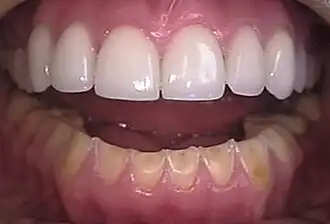

![]() Erosión en los dientes inferiores causada por bulimia. A modo de comparación, los dientes superiores se restauraron con carillas de cerámica. | ||